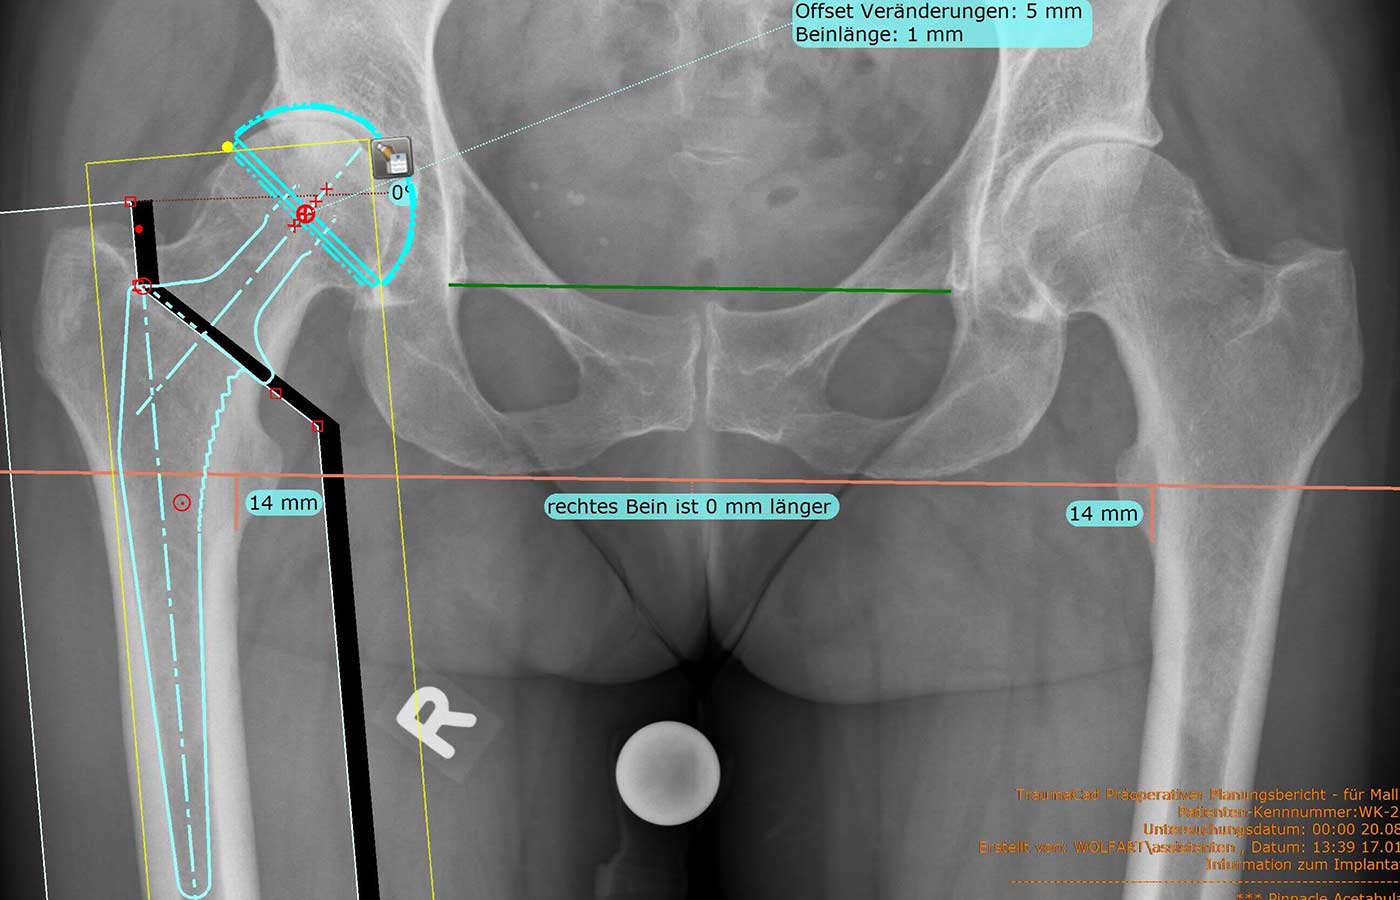

Beckenübersicht mit Prothesenplanung